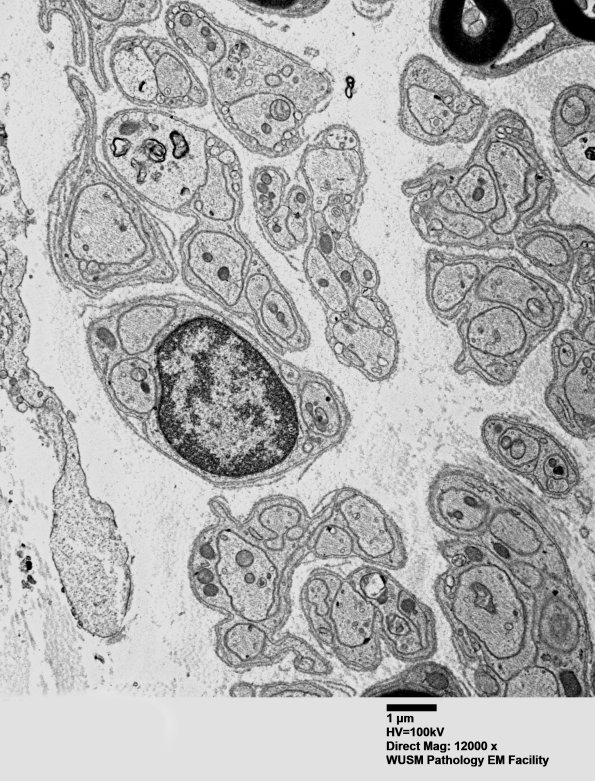

These appear to be unmyelinated axons forming Remak bundles. (electron micrograph)